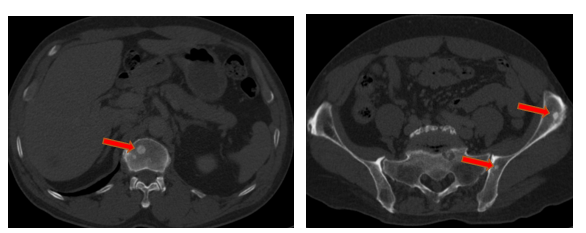

- Chụp cắt lớp vi tính ổ bụng (11/2025): Nhu mô gan phải có vài nốt, nốt lớn nhất hạ phân thùy VII có nốt giảm tỷ trọng, ngấm thuốc kém sau tiêm đường kính 8mm, hạ phân thùy II, III có nốt giảm tỷ trọng đường kính (tổn thương giảm đáng kể so với phim chụp ngày 08/2025). Các ổ đặc xương rải rác đốt sống ngực thắt lưng, xương cùng và xương chậu hai bên

Hình 11: Tổn thương ngấm thuốc kém nhu mô gan hạ phân thùy II giảm đáng kể kích thước

Hình 12: Tổn thương ngấm thuốc kém nhu mô gan hạ phân thùy VII giảm đáng kể kích thước